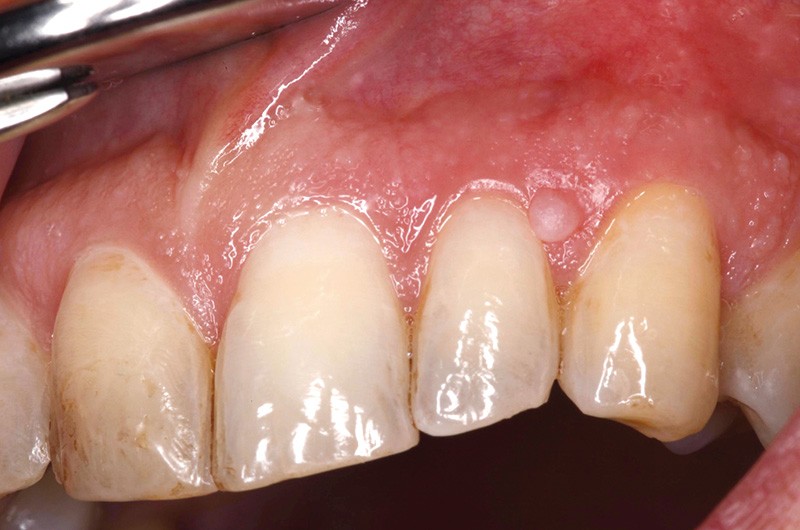

Examen clinique. La muqueuse buccale avait un aspect légèrement érythémateux, plus particulièrement celle du voile et du plancher buccal antérieur. Il n’y avait pas de mélanose tabagique, mais on observait la présence de pigment liée au tabagisme sur les dents. La lésion était constituée par un nodule ferme, de couleur rose pâle, pseudo-pédiculé, de 2 mm de diamètre, dont la base d’implantation n’était pas située directement sur le bord libre de la gencive.

Examen paraclinique. La lésion a été excisée et l’examen histopathologique de la pièce d’exérèse a montré que la tumeur était constituée par un tissu conjonctif fibreux dense, contenant quelques petits vaisseaux. Elle était revêtue par un épithélium malpighien discrètement orthokératosique, avec par endroits présence d’une fine granulose ; les crêtes épithéliales étaient élargies. Il s’agissait donc d’une petite épulis fibreuse.